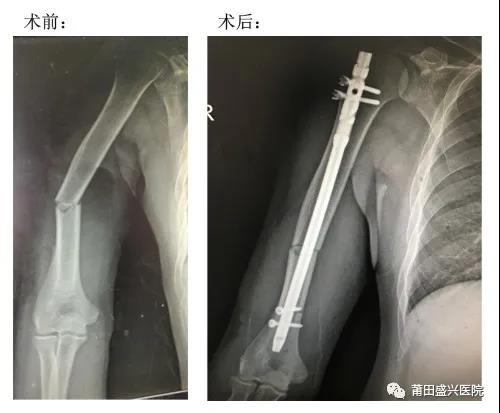

近日,我院骨科成功開(kāi)展兩例微創(chuàng )治療肱骨中段骨折手術(shù),患者術(shù)后恢復良好,均已順利出院……